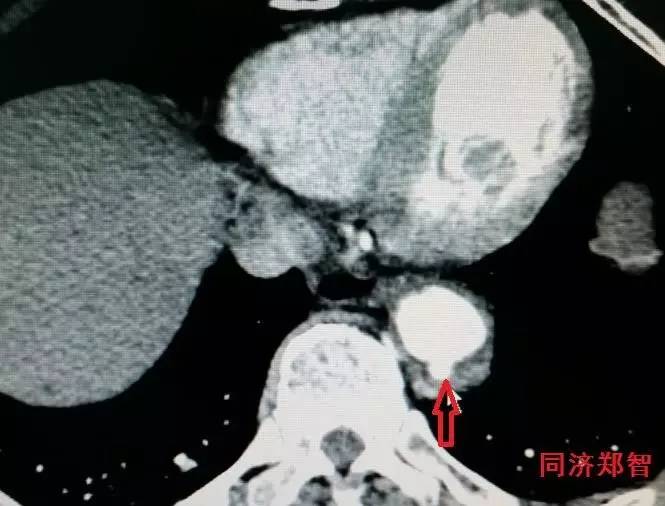

CTA显示降主动脉穿透性溃疡合并Stanford A型主动脉壁间血肿(图14)。

图14